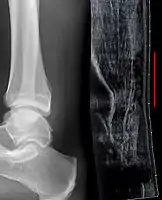

Musculoskeletal ultrasonography can be used to determine the tendon thickness, character, and presence of a tear. It works by sending extremely high frequencies of sound through the body. Some of these sounds are reflected back off the spaces between interstitial fluid and soft tissue or bone. These reflected images can be analyzed and computed into an image. These images are captured in real time and can be very helpful in detecting movement of the tendon and visualising possible injuries or tears. This device makes it very easy to spot structural damages to soft tissues, and consistent method of detecting this type of injury. This imaging modality is inexpensive, involves no ionizing radiation and, in the hands of skilled ultrasonographers, may be very reliable.

Achilles tendon rupture seen on ultrasound. Note discontinuity over several centimeters (red line). No fracture or avulsion (radiograph).